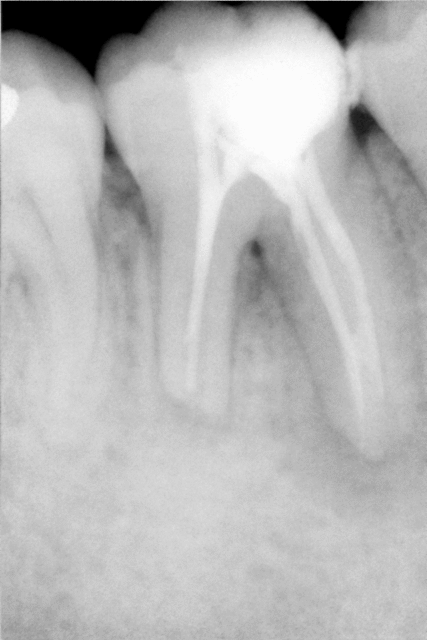

-Octobre 1998 (je sort a peine de la fac) je reçois ce jeune patient, radio n°1, je le mets sous AB, puis la semaine suivante je place un hydroxyde de calcium, la semaine qui suit je réalise l’obturation canalaire, et trois semaines plus tard l’obturation coronaire (pas de couronne mais une position pour le moins énigmatique du pivot, j’en parle avant certains mais ce n’est pas le sujet).

-Octobre 2007, mon patient pense à moi et revient me voir pour un détartrage, radio de contrôle…RAS… ? En tout cas aucun signe clinique n'est à déplorer!

-Octobre 2009 (c’est un habitué du moi d’octobre, il vient toujours me voir avant les premières palombes !!!) abcès inter radiculaire avec écoulement entre les racines…endo? paro? Je décide de faire le RT.

Dans la racine euh…distale, (à la première séance) le localisateur s’affole à 17mmm, et cela saigne abondement…je temporise avec un peu d’hydroxyde de Calcium. Apex ruiné ?

Je reprends de retour de vacances, BONNE ANNEE !!Donc lo17 pour le distal, qui saignait (je tiens a jour mes dossiers), a peine je passe une lime de 08 a 17 plus 0.01 que le saignement repart, je suis en forme je décide de fermer cet apex au MTA a n’en pas douter il est complètement explosé ! Manque de réflexion, non juste pas de radio cone en place ! Sic …

A ce stade je n’ai pas eu besoin de trop réfléchir, le patient a repris place sur le fauteuil, et j’ai vérifié la lo a la radio…lo 19mmm !!?? Je sort le bout de gutta il ne tient pas et il n’est pas souillé a l’apex ? Donc re preparation, re irrigation, et miracle, plus de saignement, je termine de façon plus conventionnelle et radio.

Bon pour l’abcès il semble que j’ai la réponse, mais quid du saignement a lo-2mm ? Réponse si le conne flottait il semble que le problème n’était pas apical. Vraiment ce saignement m’intrigue.

Je travaille sous microscope et le canal palatin (et voilà je ne me relis pas et ca recommence...distal bien sur distal ;), une erreur et tout de suite des reponses :)) avait une forme de 8, sans separation, avec ce cone de gutta de 35 invisible avant de passer au delà de 17mm, zonne dans laquelle je n'osais pas rentrer avant. Apres preparation jusqu'à la LO 19, l'apex etait bien visible le canal lateral non, et cela ne saignait plus. La zone d'ou provennait l'hemoragie contenait bien un cone de gutta!

L'apex de la racine distale n'est pas grande forme , en plus de cette probable rhizalyse , tu en as peu être une autre au milieu de la racine (en extérieur) mais au niveau de la furcation qui communique avec le canal , d'où le saignement abondant .( Je me demande si je suis clair ?!?!?).